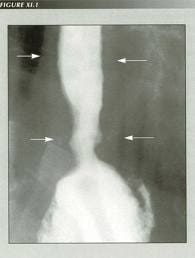

Home Esophageal Disorders: What is the role of the speech pathologist? thoracicstasis